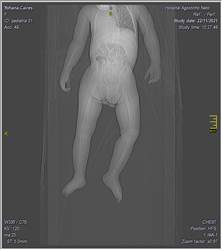

Se realizó una tomografía axial computarizada de tórax evidenciándose hipoplasia pulmonar fig. 1

Fig. 1. Tomografía axial de tórax. A. corte axial. B. corte coronal. C. corte sagital

Tomografía de tórax: Opacidad homogénea en hemitórax izquierdo con desplazamiento de las estructuras del mediastino, reducción del volumen pulmonar derecho.